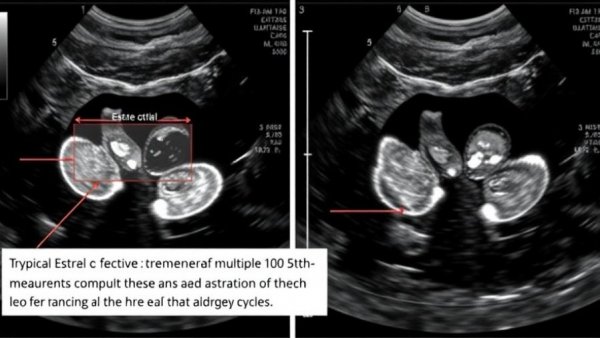

Veterinary professionals are beginning to adopt non-surgical treatments for conditions like pyometra and unwanted pregnancies. One notable method involves medical management utilizing drugs such as prostaglandins, which help manage hormonal balances and can effectively treat early pyometras or assist in pregnancy termination. In cases of pyometra, success rates vary depending on the severity of the infection and the overall health of the dog.